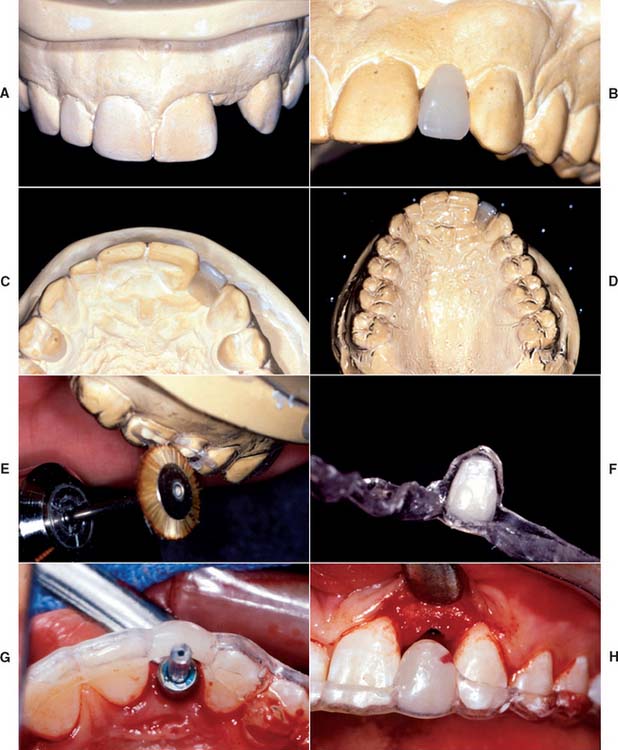

There are two distal-extension restorative options. One option is to place an implant distal to the most posterior natural abutment and fabricate a fixed prosthesis connecting the implant with the natural tooth. However, there are problems associated with implants connected to natural teeth (see p. 422). The other option is to place two or more implants posterior to the most distal natural tooth and fabricate a completely implant-supported restoration (Fig. 13-40). If the crown/implant ratio is favorable, two implants to support a three-unit fixed dental prosthesis may be considered. If implants are short and crowns are long, one implant to replace each missing tooth is highly recommended. If doubt remains, more implants are used when heavier forces are expected (e.g., the posterior part of the mouth in patients with evidence of parafunctional activity). Fewer implants are used when lighter forces are expected (e.g., those opposing a complete denture or those supporting a prosthesis in the anterior part of the mouth).

Similar options can be used to treat a long edentulous span. The clinician may choose to have multiple implants placed between the remaining natural teeth and to fabricate a fully implant-supported restoration. As an alternative, one or two implants can be placed in the long edentulous span and the final restoration connected to natural teeth. When it is necessary to connect implants and the natural teeth, protecting the teeth with telescopic copings is recommended. In this manner, prosthesis retrievability can be maintained. In addition, some long edentulous spans require the reconstruction of soft and hard tissue as well as teeth. In these instances, use of resin teeth processed to a metal substructure rather than a conventional metal-ceramic restoration is recommended. Soft tissue esthetics can be more easily and accurately mimicked with heat-processed resin and large defects (Fig. 13-41). This type of restoration is best described as a complete metal-resin fixed dental prosthesis. It has also been called a hybrid prosthesis because it combines the principles of conventional fixed and removable prosthodontics. For smaller defects, pink porcelain can be used to compensate for missing soft tissue (see Fig. 13-26B).

Fig. 13-41 A, Large mandibular defect created by a shotgun wound. B, Metal substructure of a metal-resin prosthesis tried onto three implants in this defect. C, Denture resin can more effectively recreate the soft tissue color and contours in the completed restoration than dental porcelain. D, Metal-resin restoration over the defect.